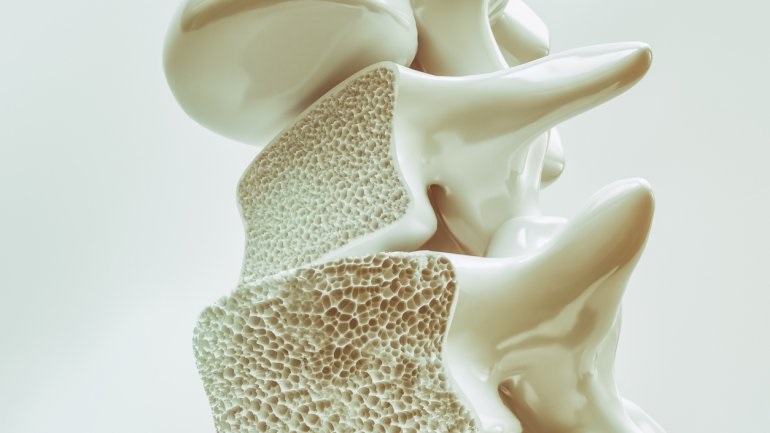

Ο περιορισμός βάδισης αυξάνει τον κίνδυνο κατάγματος

Ο περιορισμός στο περπάτημα σχετίζεται σημαντικά με τον κίνδυνο κατάγματος σε μια διάρκεια 4-5 ετών, σύμφωνα με μια μελέτη που δημοσιεύθηκε στο JAMA Network Open.